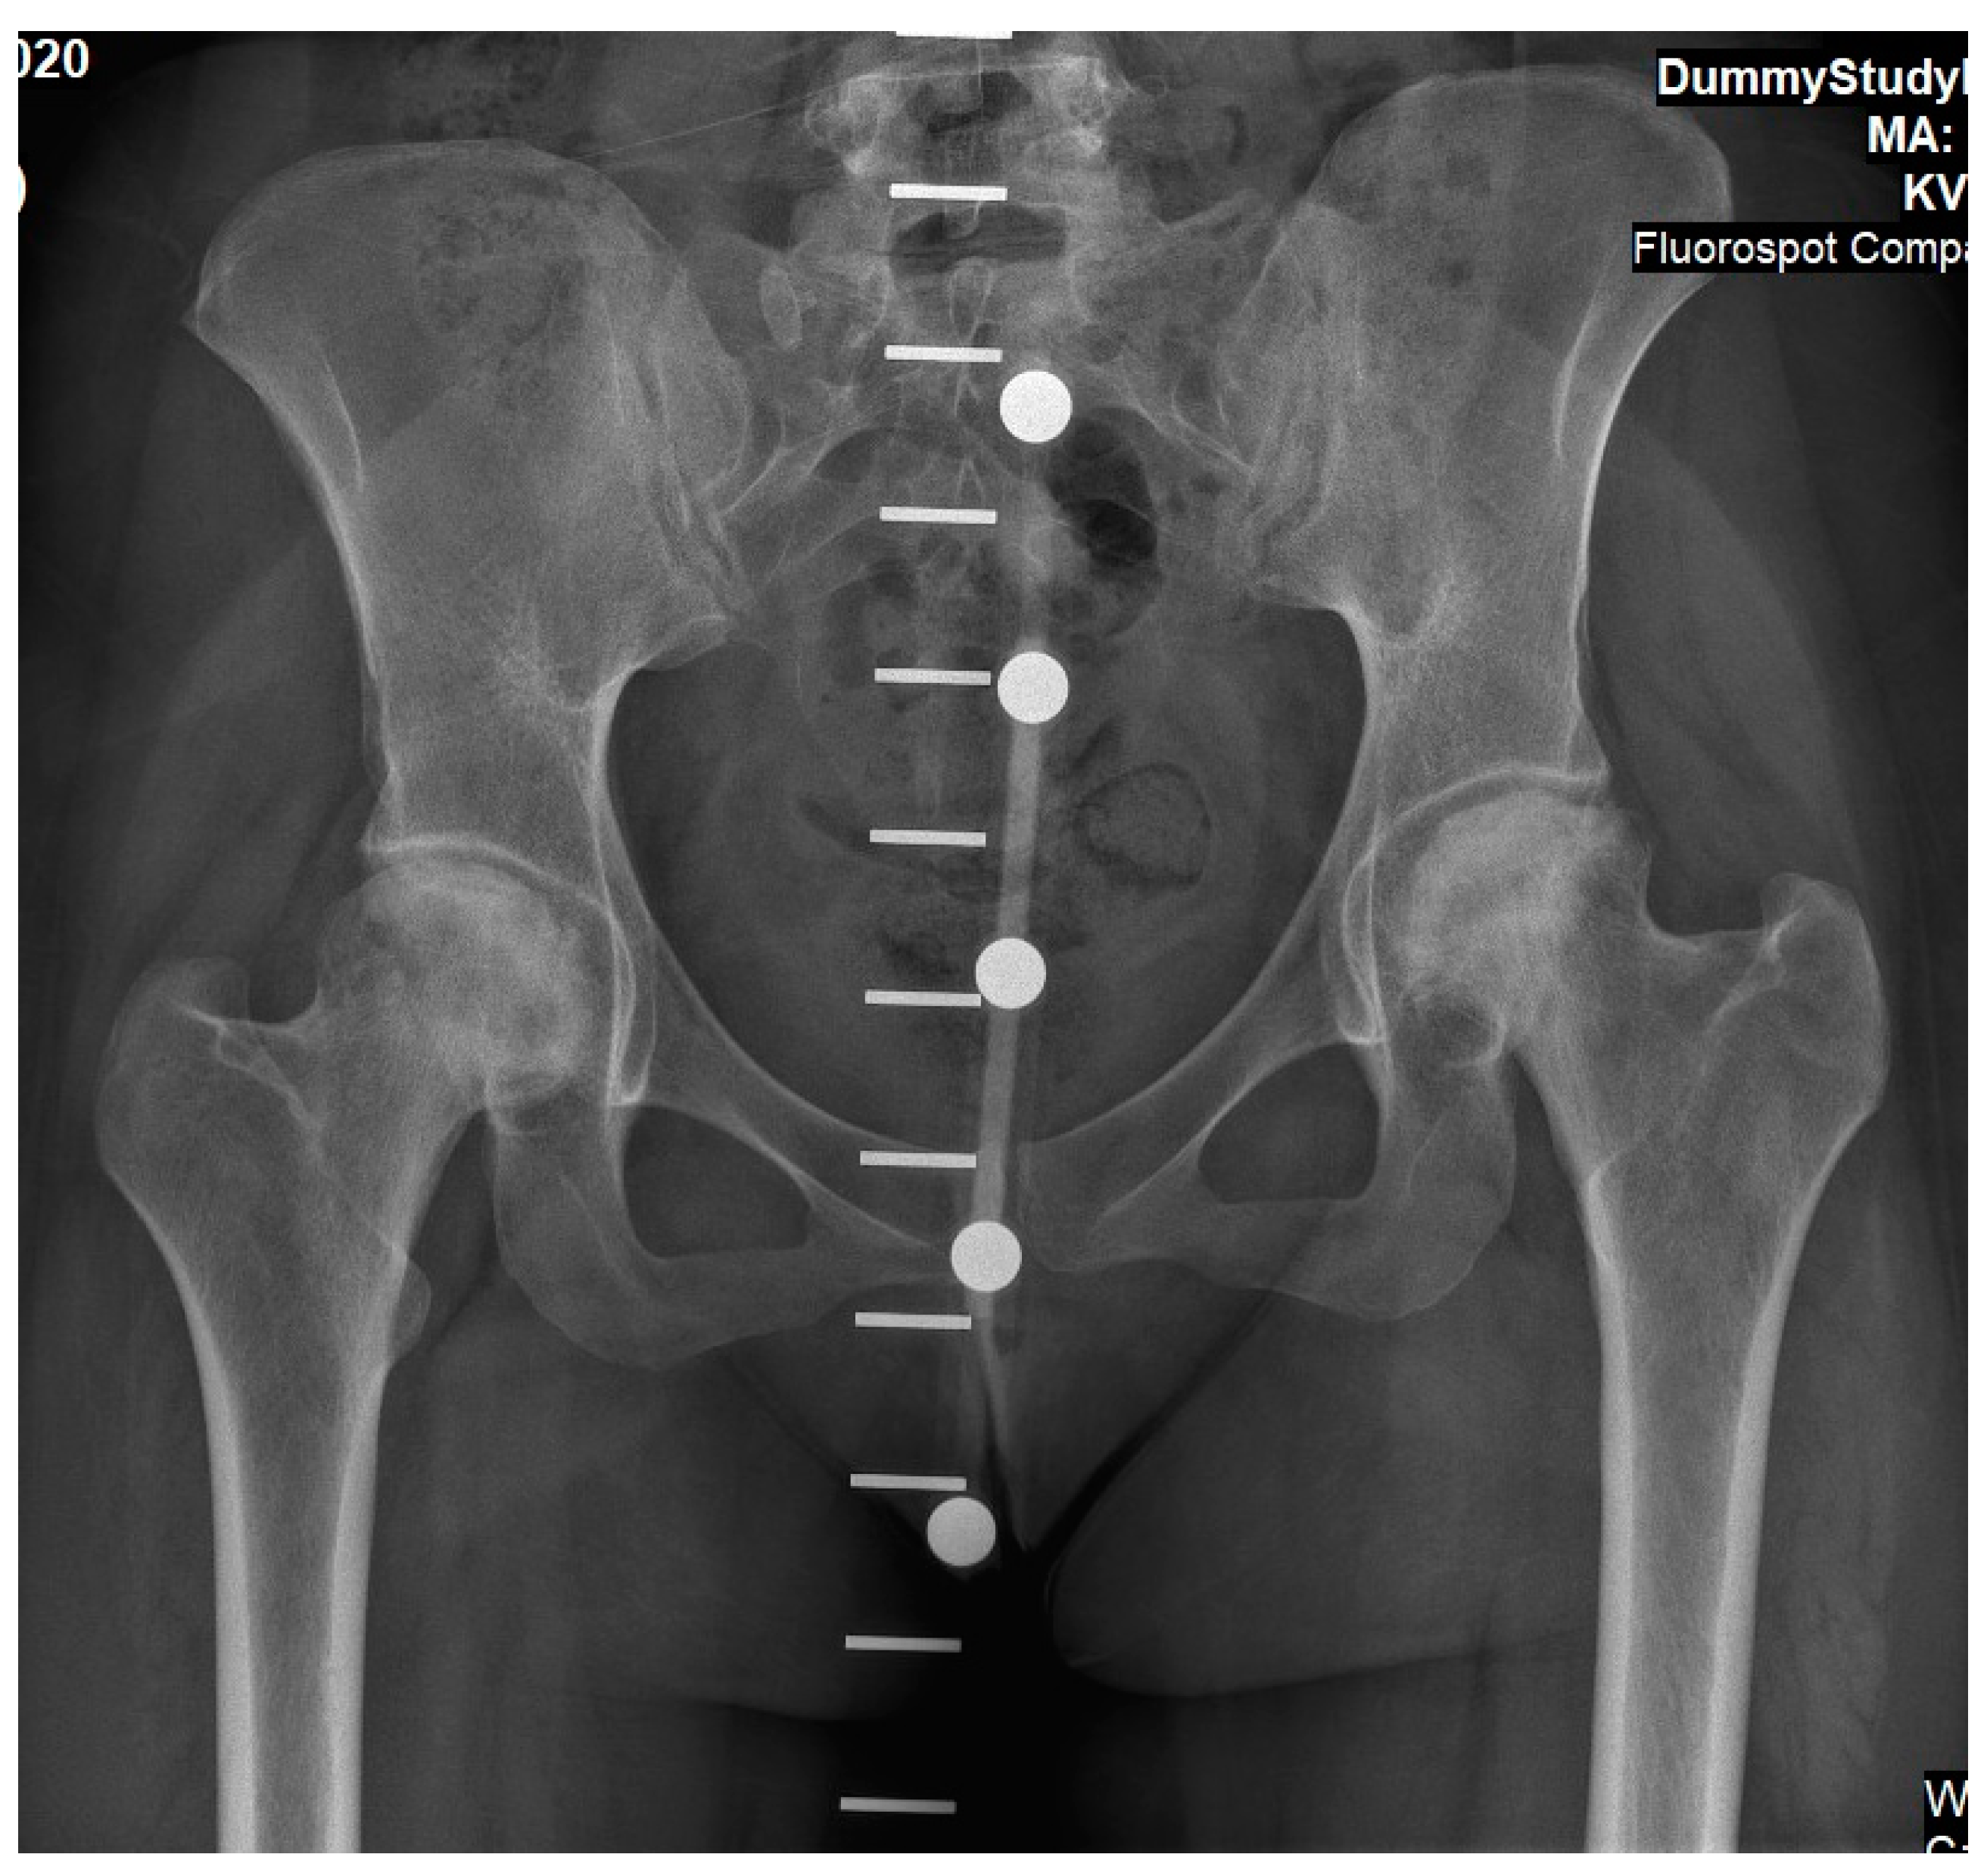

Figure 4.

An antero-posterior X-ray of pelvis and hip joints of Case 2. This was taken as part of pre-operative planning for simultaneous bilateral hip arthroplasty (note the calibration marks used for implant selection). At this stage she was in severe pain. These findings present osteonecrosis changes to femoral heads, although sphericity is partially preserved and joint space is still evident.